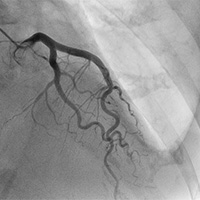

1. 心臓カテーテル検査

手首や足からカテーテルを通して、心臓を栄養している血管(冠動脈といいます)を造影して、細くなったところを探していきます。

右冠動脈

左冠動脈